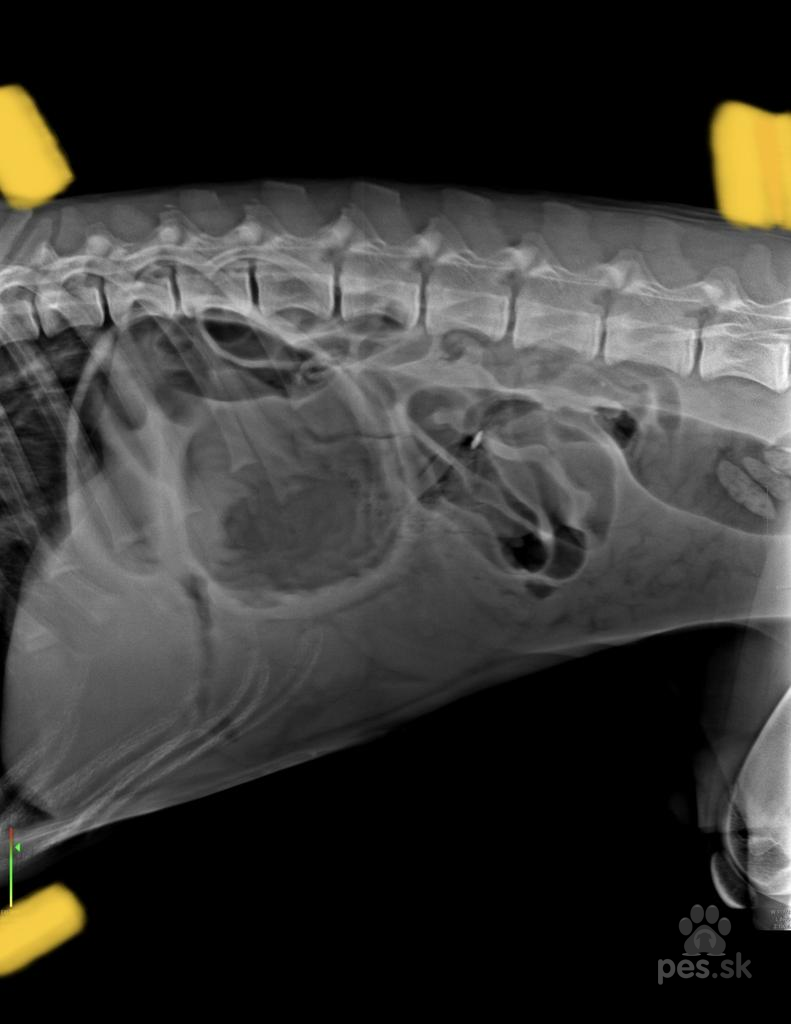

Dobrý deň, chcela by som Vás poprosiť o názor či u nášho psíka bola torzia žaludka podla rontgenovych snimok. Pretoze sme boli zoperovany vraj na ciastocnu torziu, ale priznaky torzie sme nemali. Jedine co bola plynatost..Prikldam rontgenovy snimok, prekryla som udaje o klinike kde bol moj psik robtgenovany a operovany, nechcem hanit ich meno. Dakujem za odpoved. Prajem pekny denVeterinár radí - bezplatné poradenstvo pre vášho psíka

Dobrý deň, chcela by som Vás poprosiť o názor či u nášho psíka bola torzia žaludka podla rontgenovych snimok. Pretoze sme boli zoperovany vraj na ciastocnu torziu, ale priznaky torzie sme nemali. Jedine co bola plynatost..Prikldam rontgenovy snimok, prekryla som udaje o klinike kde bol moj psik robtgenovany a operovany, nechcem hanit ich meno. Dakujem za odpoved. Prajem pekny denOdpovede veterinárov

ano podla RTG snimku to vyzera na torziu zaludka.